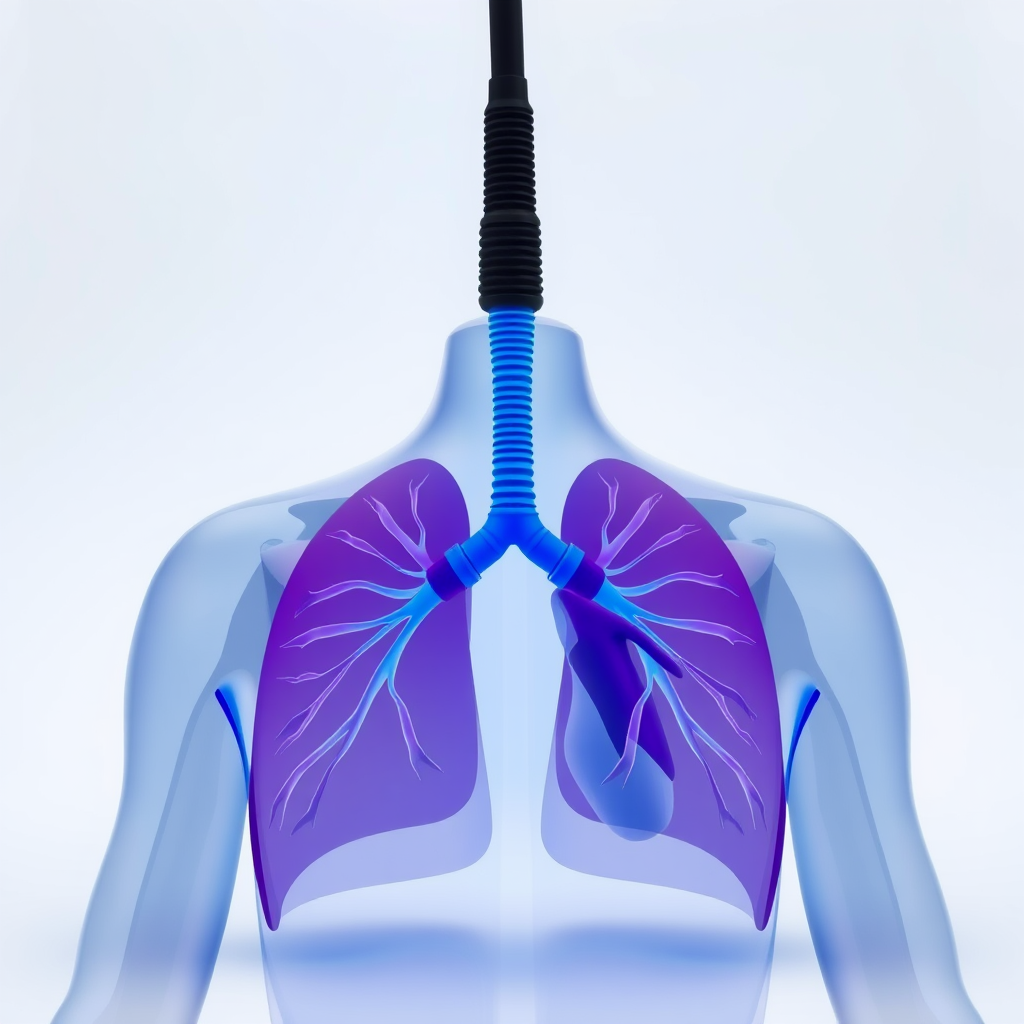

Um dos principais benefícios da fisioterapia cardiorrespiratória é a melhora da função pulmonar.

Na clínica de fisioterapia cardiorrespiratória em São Paulo, os exercícios respiratórios ajudam a expandir os pulmões e aumentar a eficiência da respiração.

Isso é especialmente relevante para pacientes com doenças pulmonares crônicas.